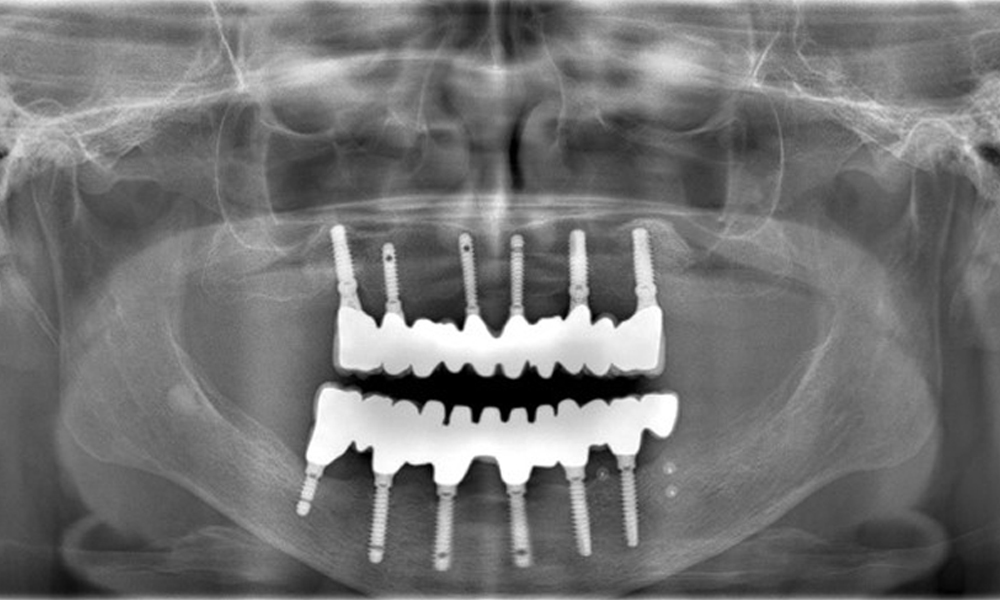

Provisions: Implants in regions 011, 013, 015, 021, 023, 025, 031, 033, 035, 042, 044, 046

The radiographic images reveal bone resorption.

Figure 2: The radiographic images reveal bone resorption.